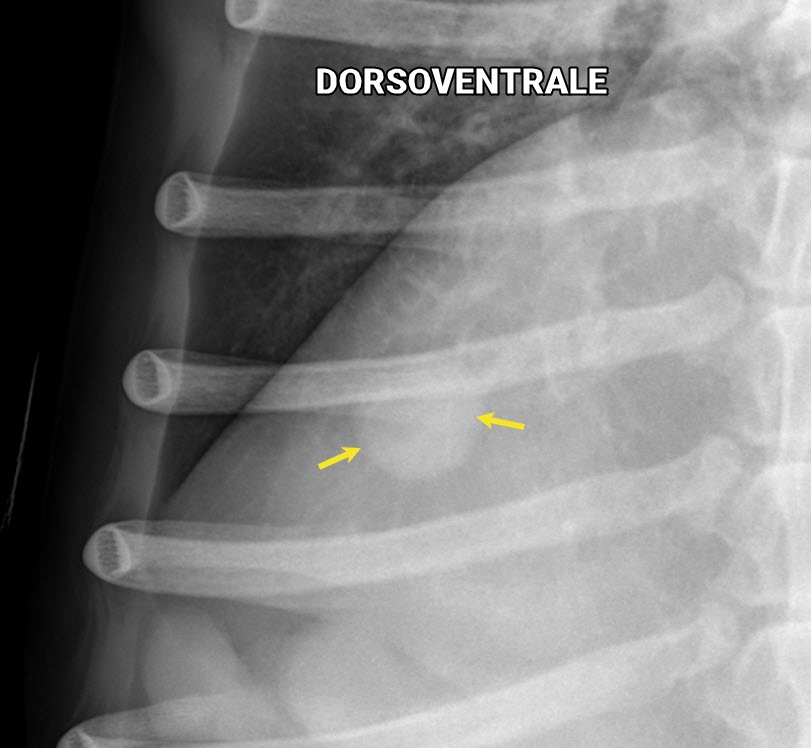

Voici un chat domestique de 7 ans mâle castré présenté pour suivi de sa condition cardiaque. En plus de l’évaluation de la silhouette cardiaque, un examen attentif des vaisseaux pulmonaires crâniaux et caudaux est requis.

En comparant les deux projections, on peut apprécier que la dorsoventrale met davantage en relief les vaisseaux des lobes caudaux (flèches jaunes). On peut aussi y voir que l’extrémité caudale des lobes pulmonaires s’étend plus caudalement en DV (flèches noires), confirmant leur plus grande insufflation.